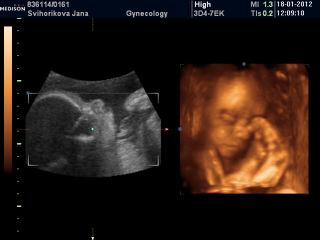

Ahojte babulky, tak sjme doma z utz..mala je nadherna, sice stale mensi, dneska jsme 27+1, ale zodpovidame na na 25+6, ale to uz od zacatku vime...jen zla poloha☹stale chudak je zkroucena v 1/4 bricha, je to tim, ze mam dvourohou delohu a mala se tam nevejde☹z 90% se z teto polohy nedokaze sama vykloubit a na radu prichazi sekcie☹

CD mam plne fotek, ale ne moc kvalita, jak vuci mista v maternici, tak tim ze je mala natlacena a neni misto, kde by se dalo na ni podivat...pry se k nim mam objednat jeste na morfologicky v 30tt a ze kdyz to bude lepsi, tak mi na to CD doplni dalsi fotky gratis, no fakt mila baba, hrozne prijemna, necelou hodinu s enam venovala aza ty penize to fakt stoji...

Na prvni fotce je krasne videt, jak ma oblicejik, rucicku a jeste aj nozicka, chudak je fakt v ulite, nema tam misto, snad to nebudou do budocich tydnu komplikace